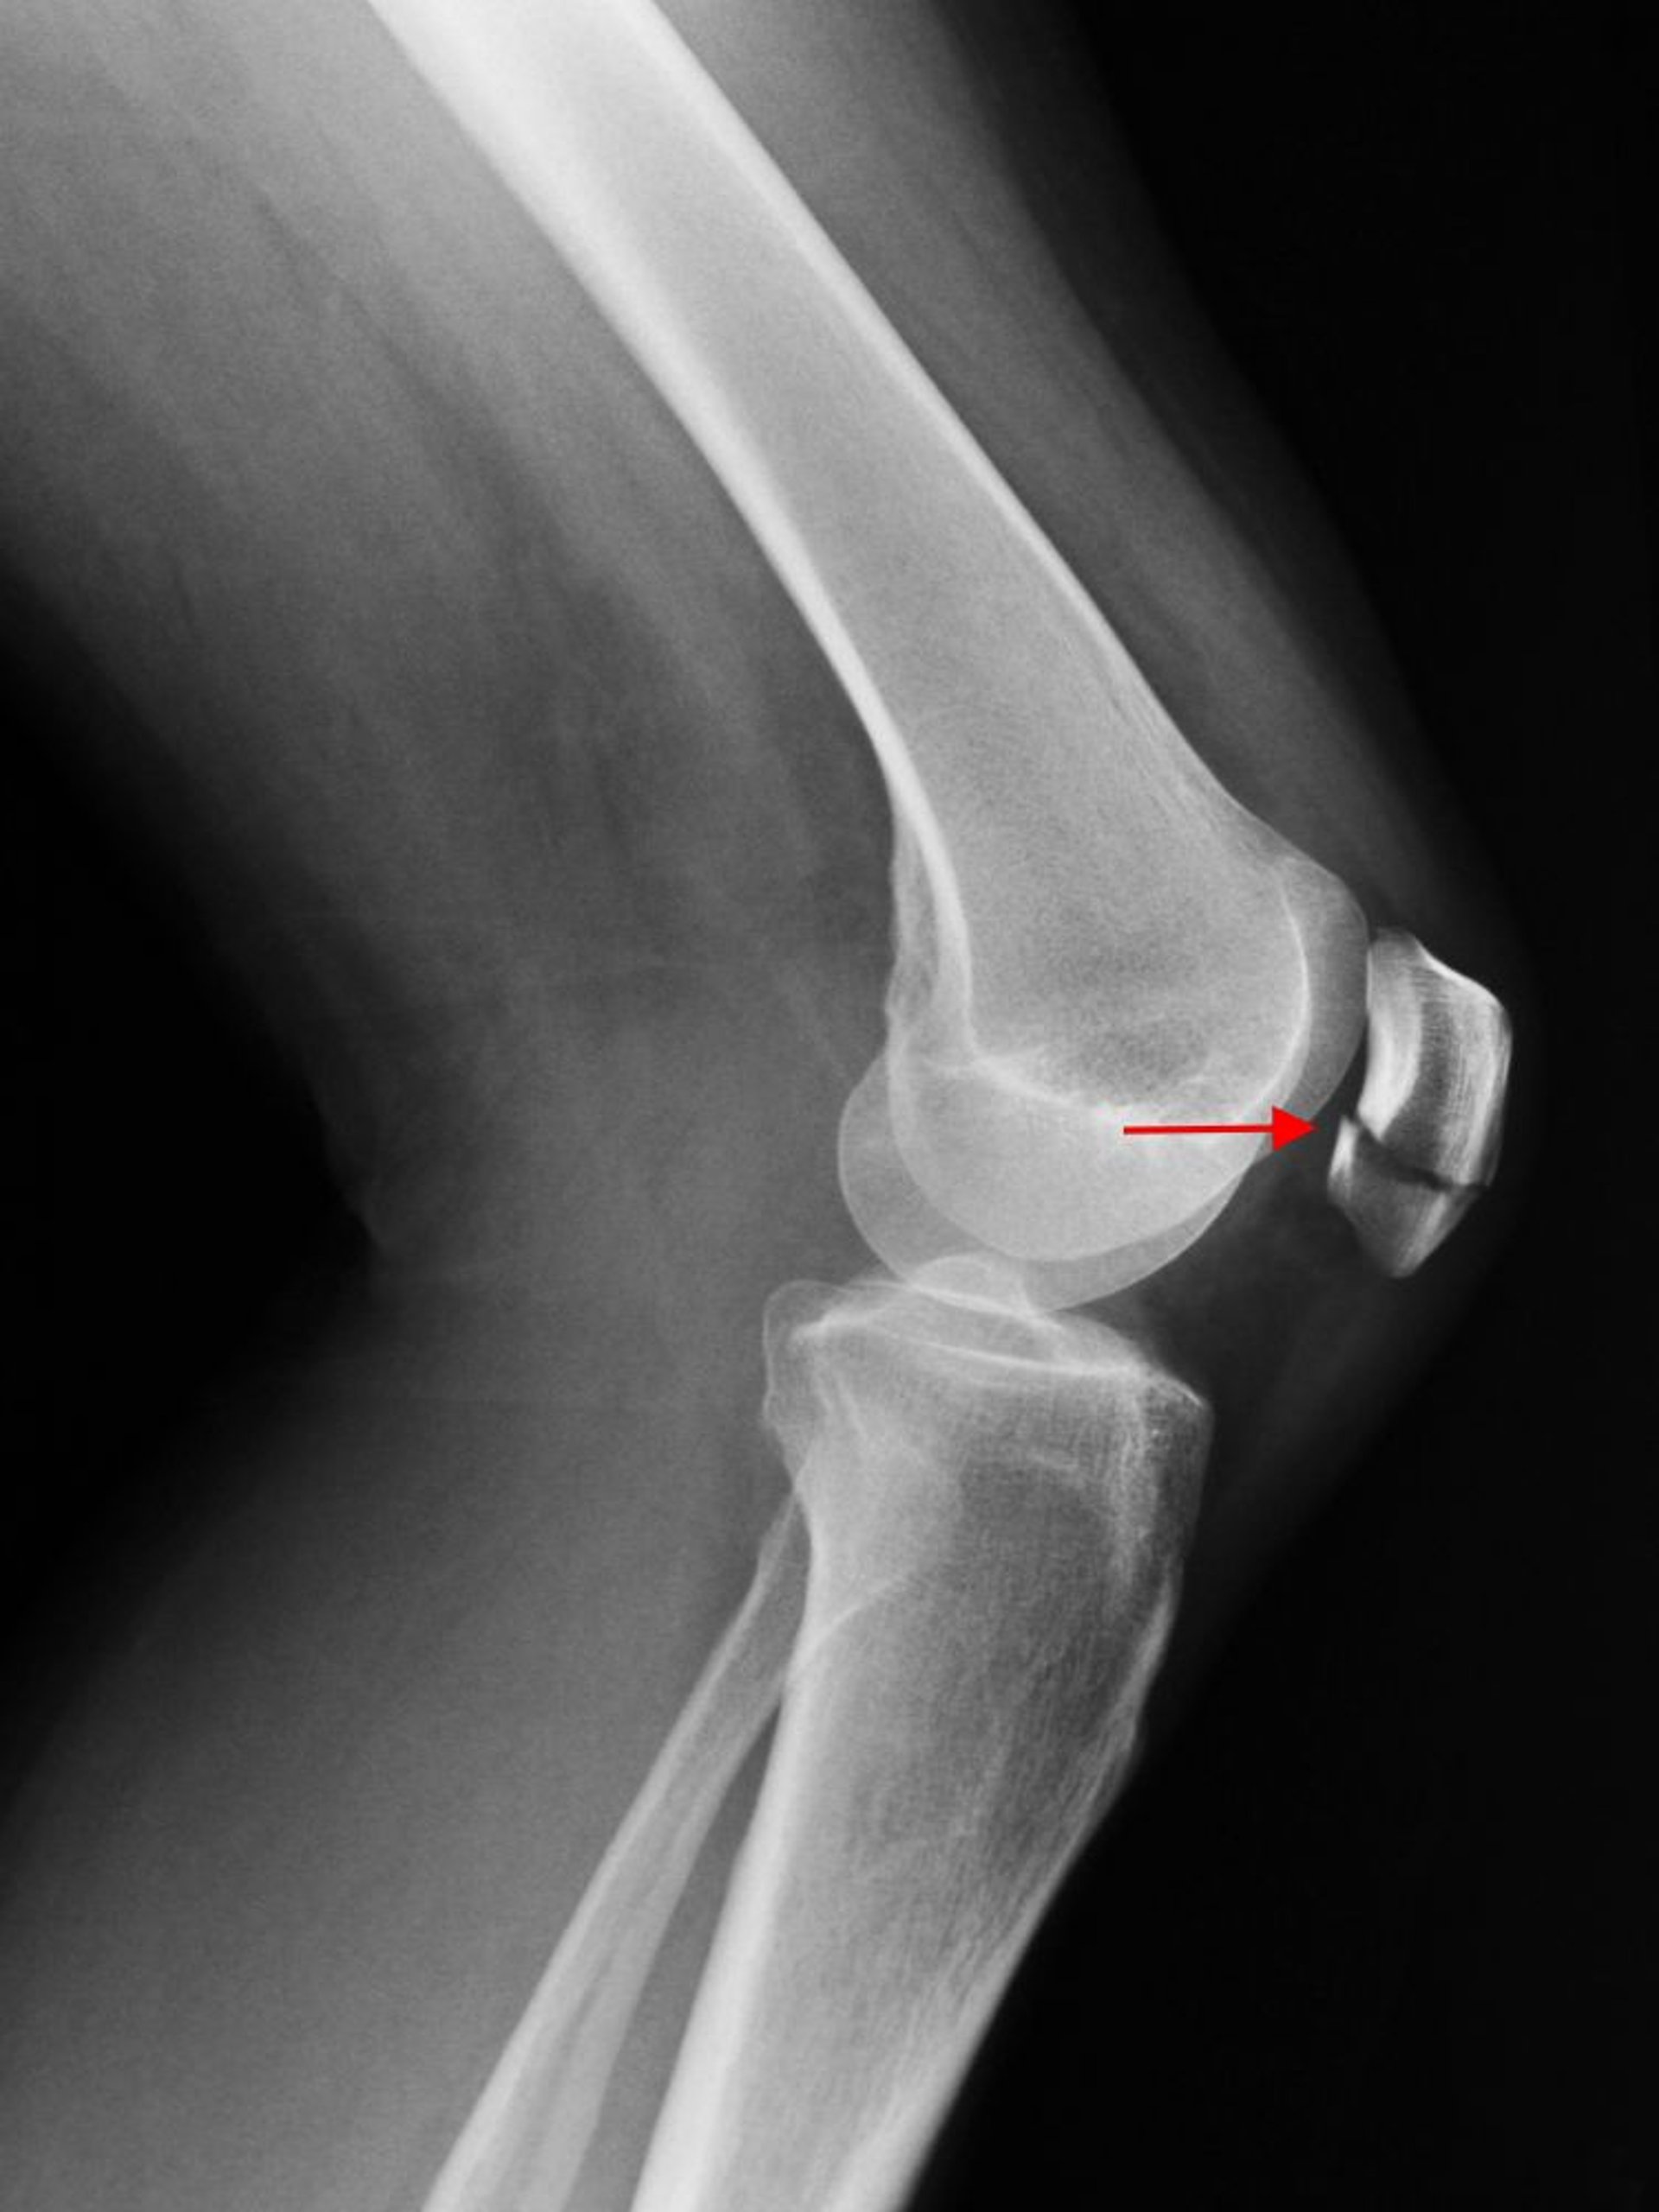

Patellar Fracture

A lateral knee radiograph shows a transverse fracture of the patella (arrow).